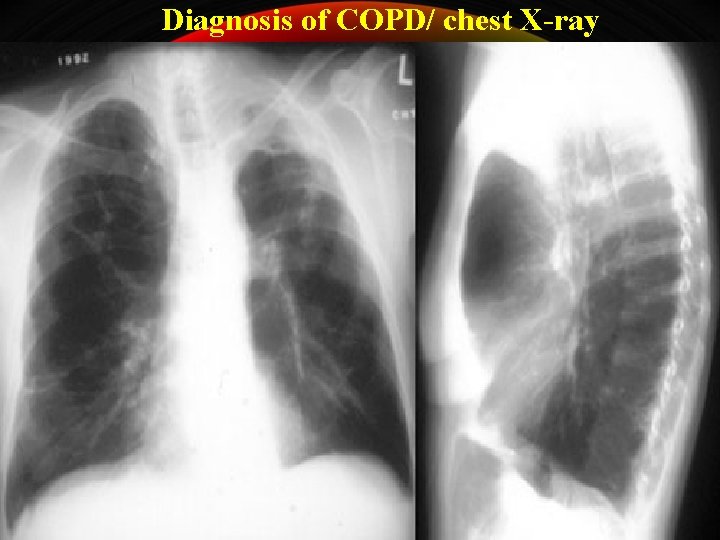

Diagnosis of COPD/ chest X-ray